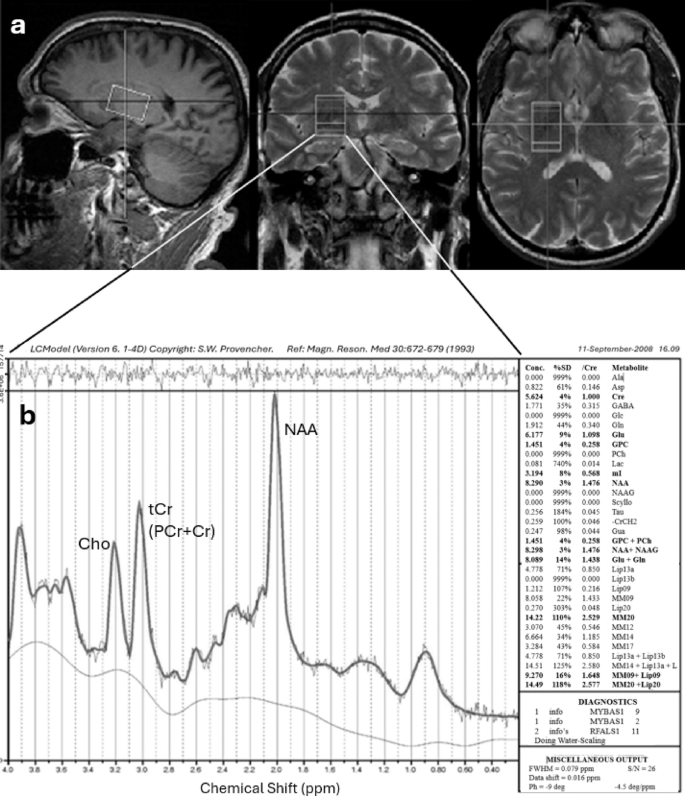

Localized 1H-MRS data were collected using a single-voxel point-resolved spectroscopy sequence (PRESS) on a Siemens 3T Trio total imaging matrix (TIM) MR system with a 12-channel head coil and TR = 2500 ms, TE = 30 ms (96 averages, acquisition time = 4:10) and 270 ms (64 averages, acquisition time = 2:47). Single voxels were centered in the putamen bilaterally, catching small corners of the caudate head and anterior thalamus, and excluding ventricular cerebrospinal fluid [CSF] with volume = 12.0 mL (20 mm x 30 mm x 20 mm, LR/AP/IS) (Fig. 2A). It had spectral width = 2000 Hz, water suppression bandwidth = 50 Hz, data points = 1024. An unsuppressed water spectrum with eight averages was acquired for eddy current compensation25 and quantitation.

Acquisition of spectra from a Gulf War veteran with LCModel to estimate concentrations of N-acetylaspartate (NAA), total creatine (tCr) and choline (Cho). (A) Spectroscopy voxel positioning in the right basal ganglia. (B) A 3T 1H-MR spectrum (TE = 30 ms) of the left basal ganglia of a representative subject processed using LCModel. Metabolites detected with acceptable reliability are shown in bold font in the table on the right.

High resolution localizer images in 3 orthogonal planes were used in combination with Siemens AutoAlign to ensure accurate and reproducible voxel positioning among subjects and across multiple scan sessions within subjects and avoiding white matter and ventricles to prevent confounding by tissue type26 (Fig. 2A). Magnetic field homogeneity was achieved by standard auto-shim followed by first order manual shimming.

Metabolite half-height line widths were 9–14 Hz. Cramer-Rao lower bounds were 3–4% for [tCr], [NAA], and [tCho] fits. Less than 3% of data sets for T2 calculations were rejected due to poor fit quality. A typical example of a spectrum is shown in Fig. 2B.